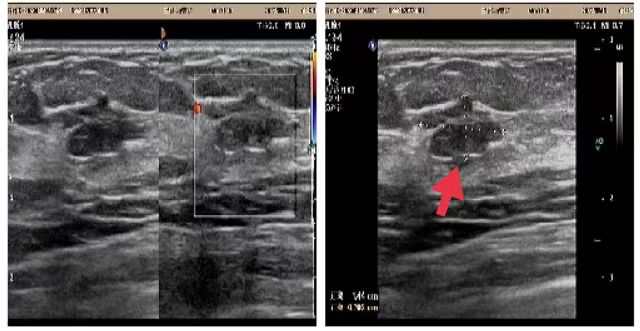

03、**女士,62岁

于2023年8月12日在邯郸仁泰东区体检,甲状腺彩超检查提示:甲状腺大小正常范围,腺体内多发结节,较大位于右叶,大小约2.9*1.4cm中等回声结节,内回声不均匀,右叶另见低回声结节,大小约0.97*1.1cm,边界欠清,内见多发强回声团。2023年8月13日首次回访,通知客户到专科医院进一步检查和治疗。2023年8月30日跟踪回访,客户告知接到电话后分别去河北工大附属医院和邯钢医院检查,结果与我院检查结果一致,已选择在邯钢医院手术治疗,目前正在恢复中。